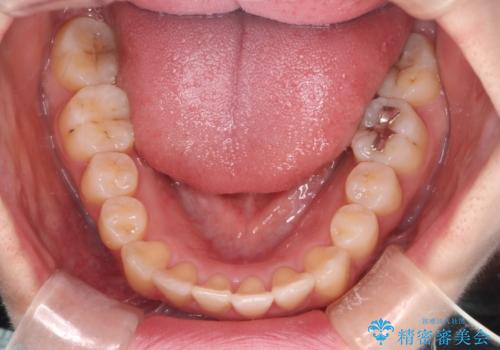

【インビザライン】マウスピースで開咬改善

- 開咬を主訴に来院されました。

IPR(歯と歯の間を削る処置)と顎間ゴムを行いながら、インビザラインで開咬を治療する計画を立てました。

治療をしながら、MFT(口腔筋機能療法)も行っていくことにしました。

歯の移動量が多いケースでしたが、患者様にマウスピースの使用とゴム掛けを頑張っていただいたので

リファイメント1回のみで治療を終わることができました。